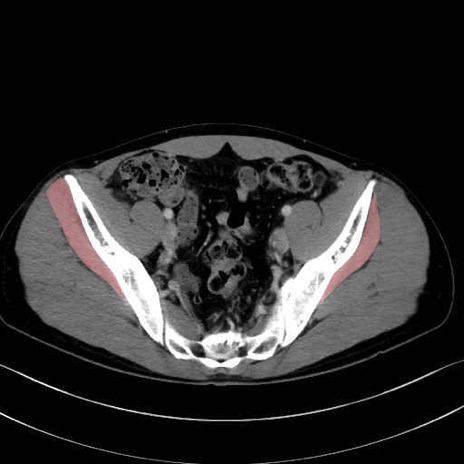

小殿筋 (Gluteus minimus)